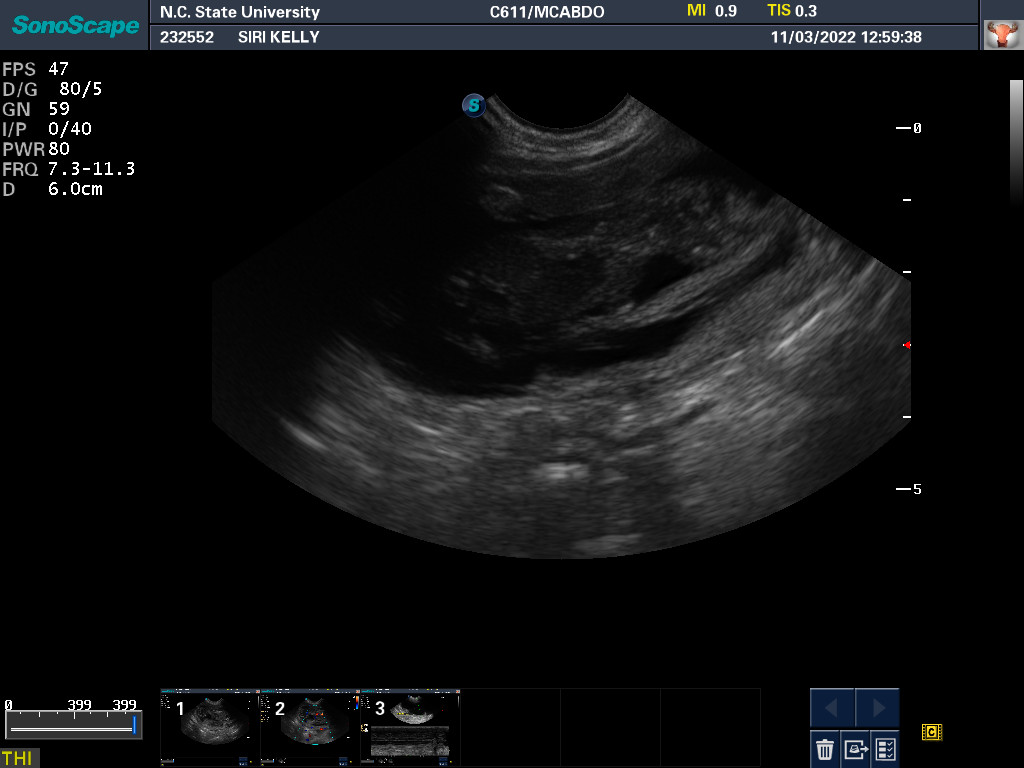

3 Nov 2022

Ultrasound today by the theriogenology (reproduction) veterinarians at NC State University showed that Siri is pregnant with possibly two puppies. It is difficult to accurately count puppies using ultrasound.

If all goes well, puppies are due around 28 November.